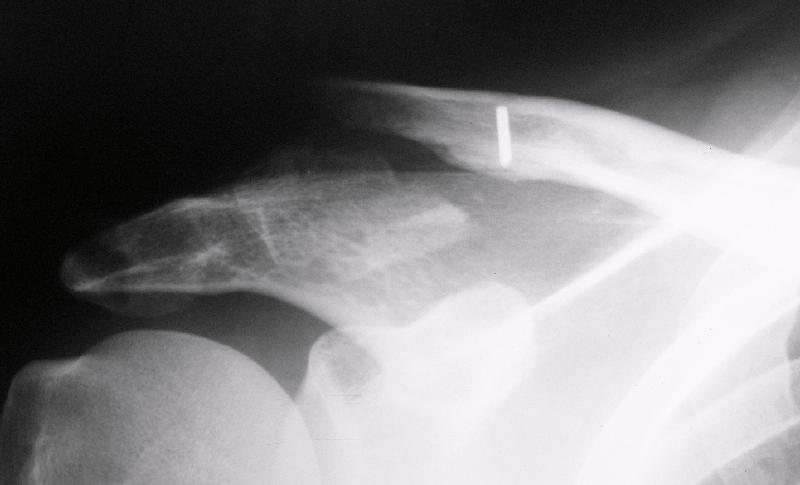

АПК> молодому пациенту по поводу оскольчатого перелома акромиального конца

АПК> ключицы

Что за редкая травма? Никогда такой не видел... Покажите?

АПК> После перелома "толкателя"

Что за перелом "толкателя"?

Судя по представленному снимку - существует дистальный фрагмент, который замечательно, вроде бы, связан с акромионом... Что мешает "пришпилить" проксимальный к дистальному и закрепить его при помощи спиц? или как-то по иному (аппарат?)... В любом случае зачем пока идти большим разрезом на ключично-клювовидную связку? почему не пойти от меньшего?

"Толкатель" - укороченная спица с упором. На первичных снимках - оскольчатый перелом, отдельный фрагмент с местом прикрепления кл-кл связки сместился каудально.